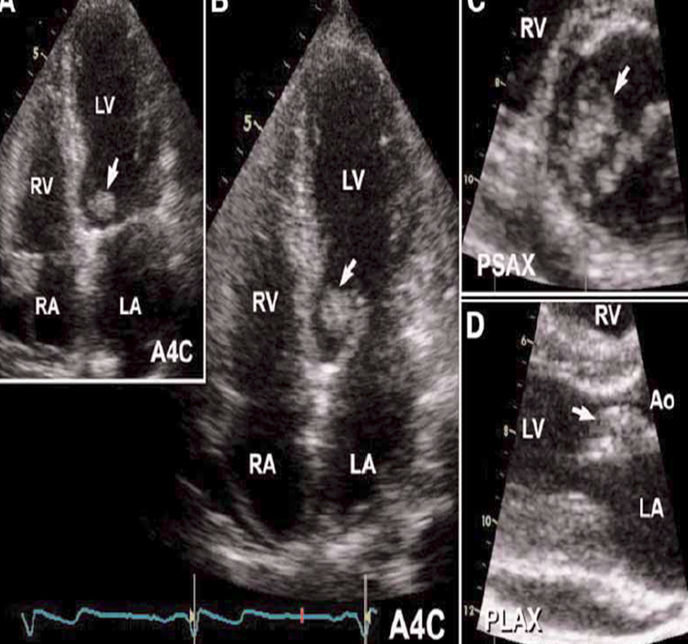

what is shown here?

ao valve vegetation with abscess

what is seen here?

endocarditis vegetation of tricuspid leaflets and infectious abscess of aortic annulus